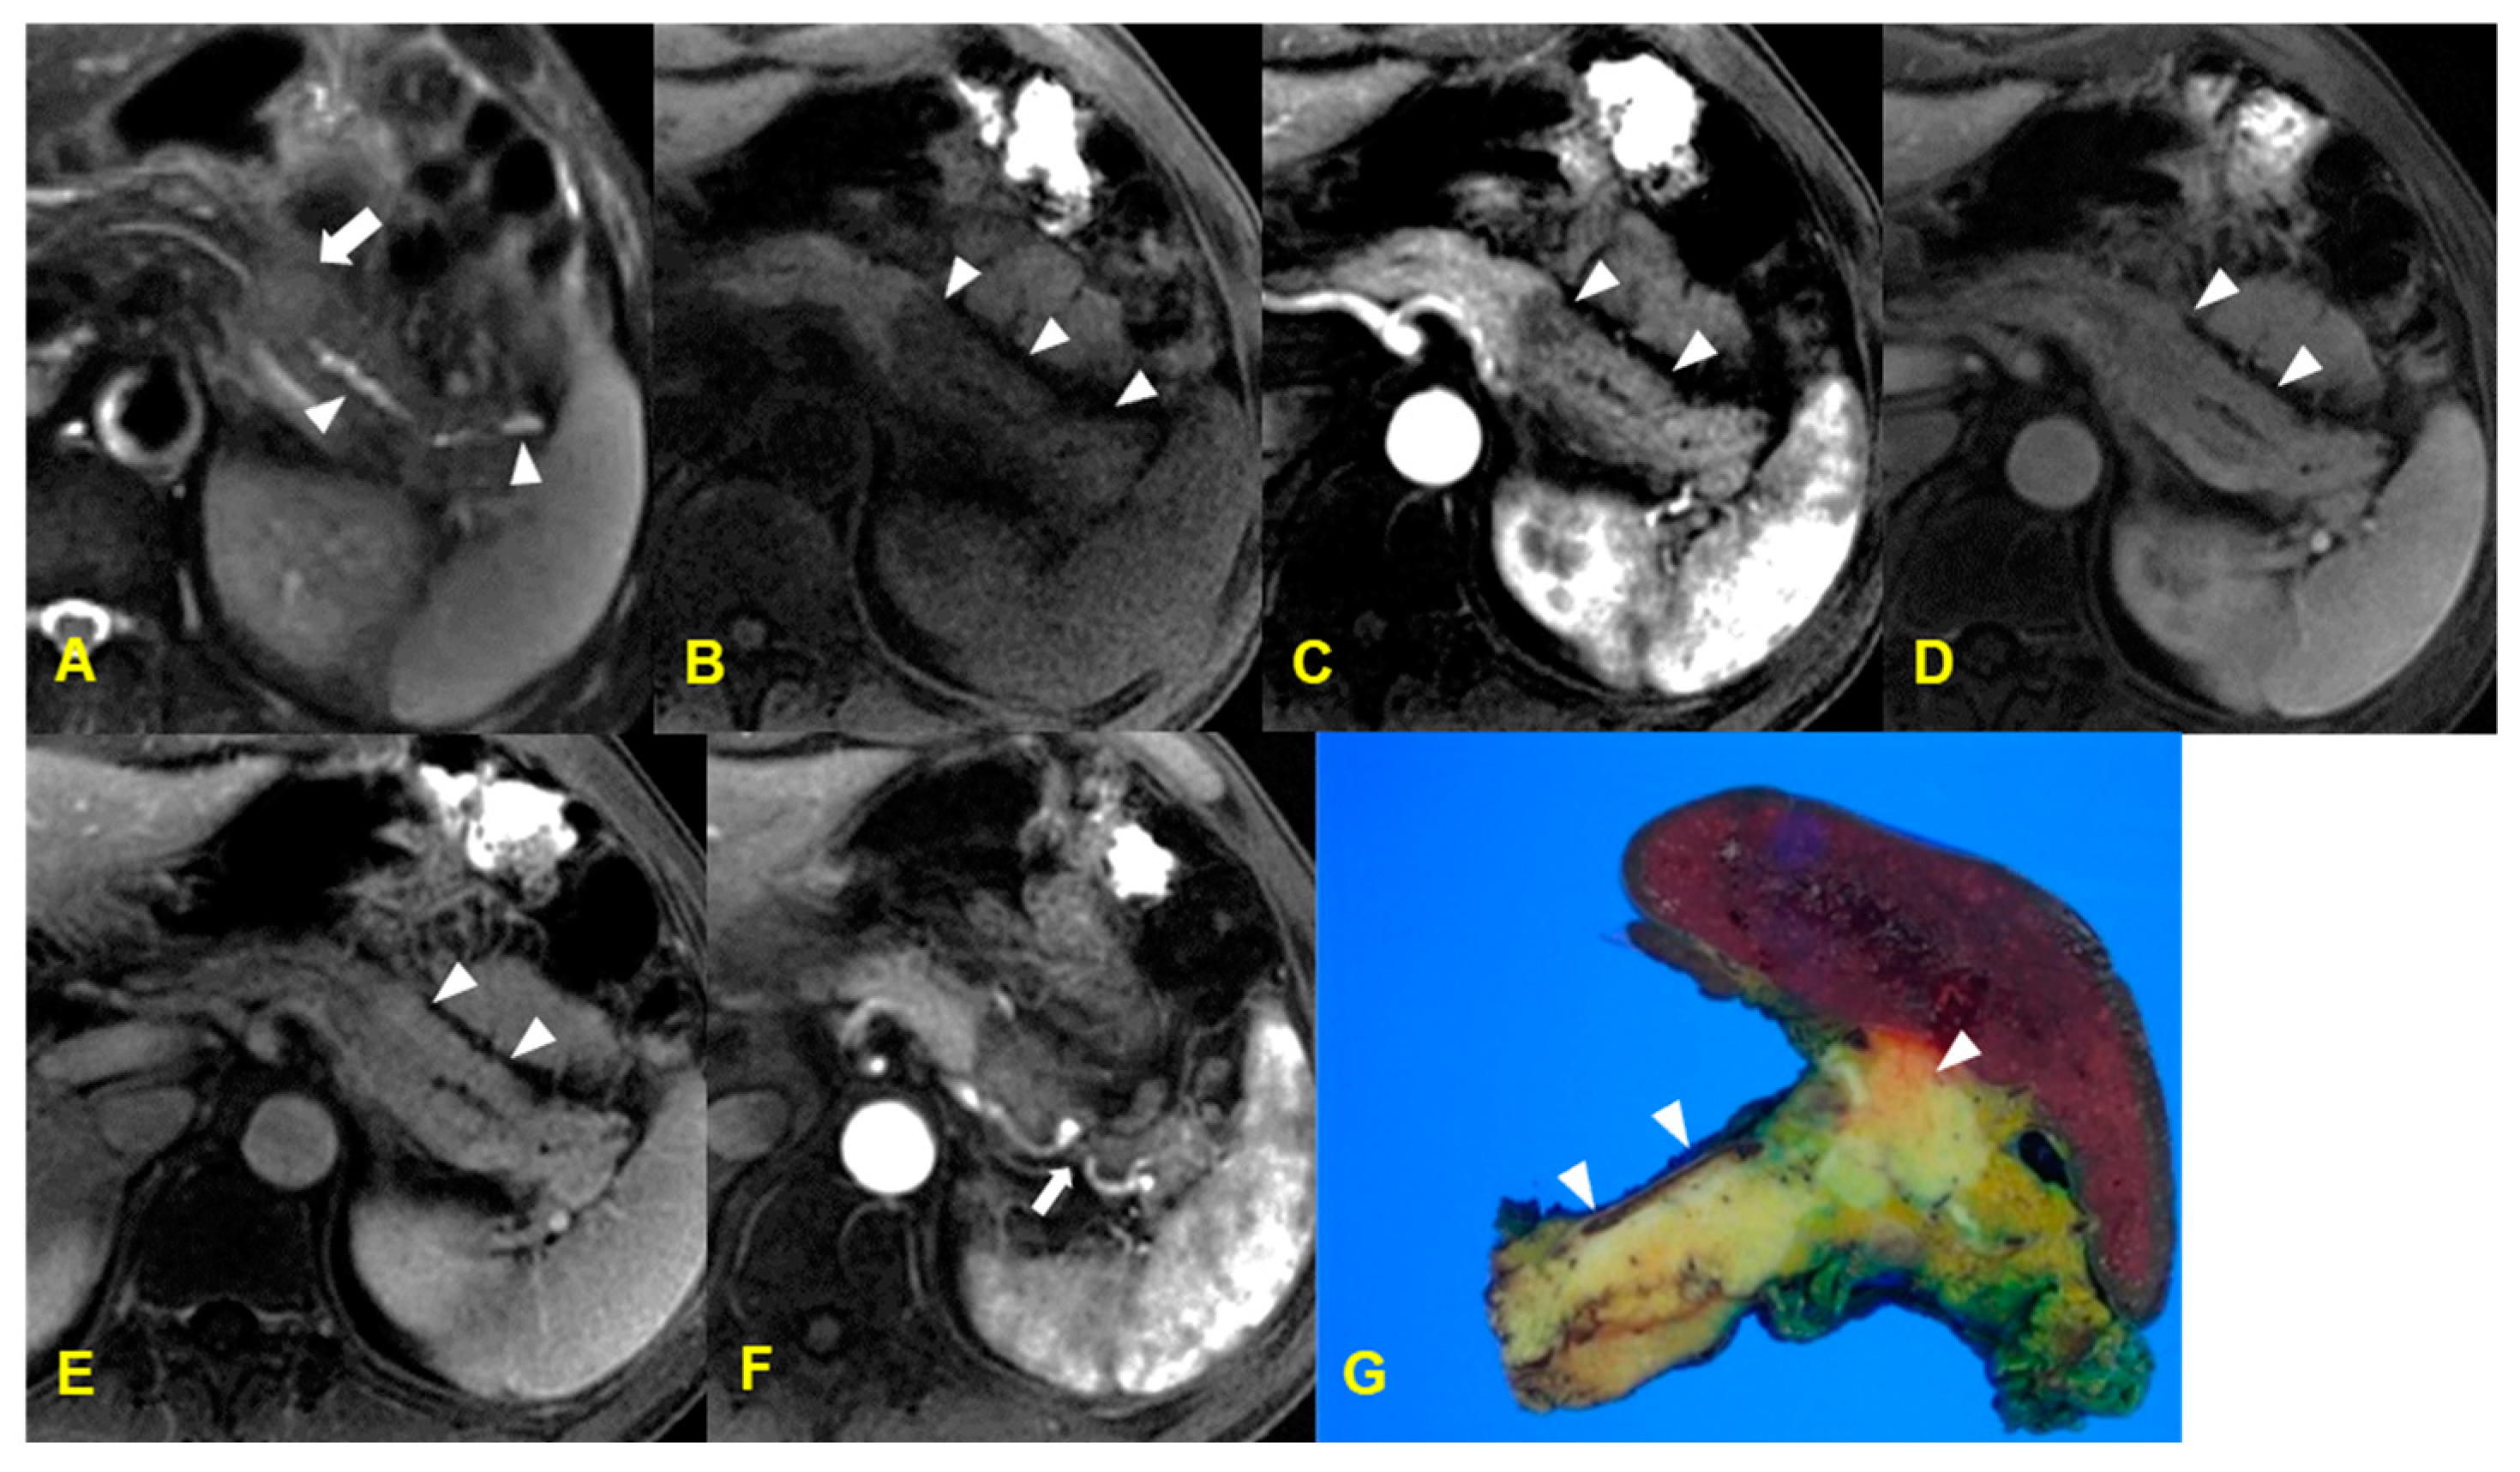

9. Autoimmune Pancreatitis

9.1. Imaging Finding

9.2. Differential Diagnosis

| Autoimmune pancreatitis | Diffuse type: enlarged pancreas with sausage-like appearance |

| Focal type: relatively well defined with delayed enhancement | |